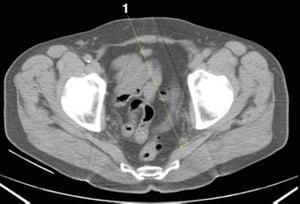

CT-Scan von Abdomen und Becken mit normaler Anatomie ohne Kontrastmittel (Folie 26)

1 = M. piriformis.

© Springer Science+Business Media